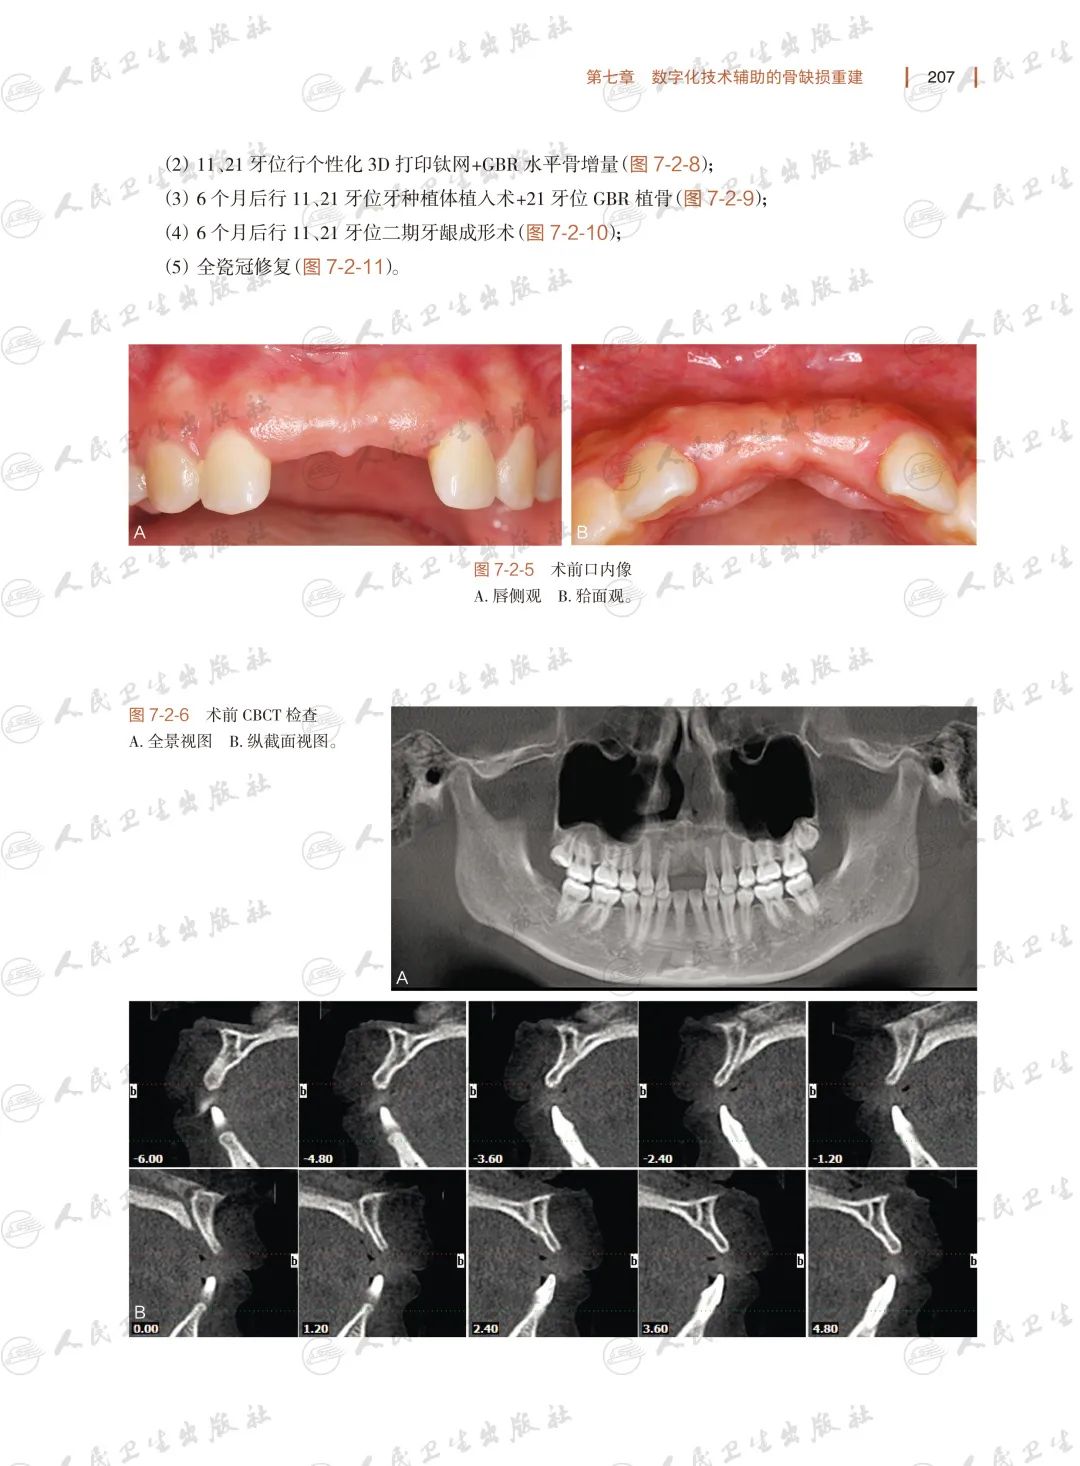

数字化技术在骨缺损重建口腔外科中的应用